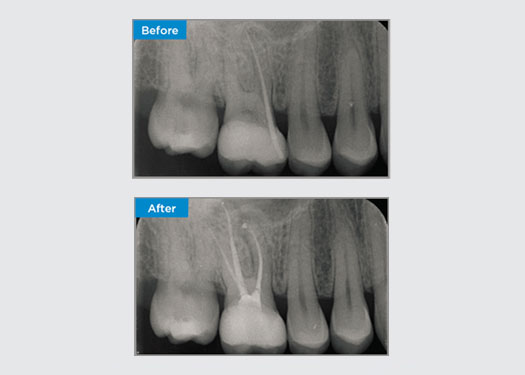

The patient was presented with irreversible pulpitis on tooth 46. From the pre-op radiograph, tooth 46 is presented with an additional distal root (Radix Entromolaris tooth morphology). A CBCT scan has confirmed the presence of DL root with severe root curvature. A careful file selection is critical for this delicate DB root.

Dr Jack Lin, Endodontist, Sydney, NSW Australia

In this situation, tooth/root structure preservation is essential to reduce the risk of ledging, transportation, zipping, perforation, and root fracture. Case selection, diagnosis, and pre-treatment planning are important. Endodontic file selection with flexibility, efficiency, and respect of natural root anatomy is critical.